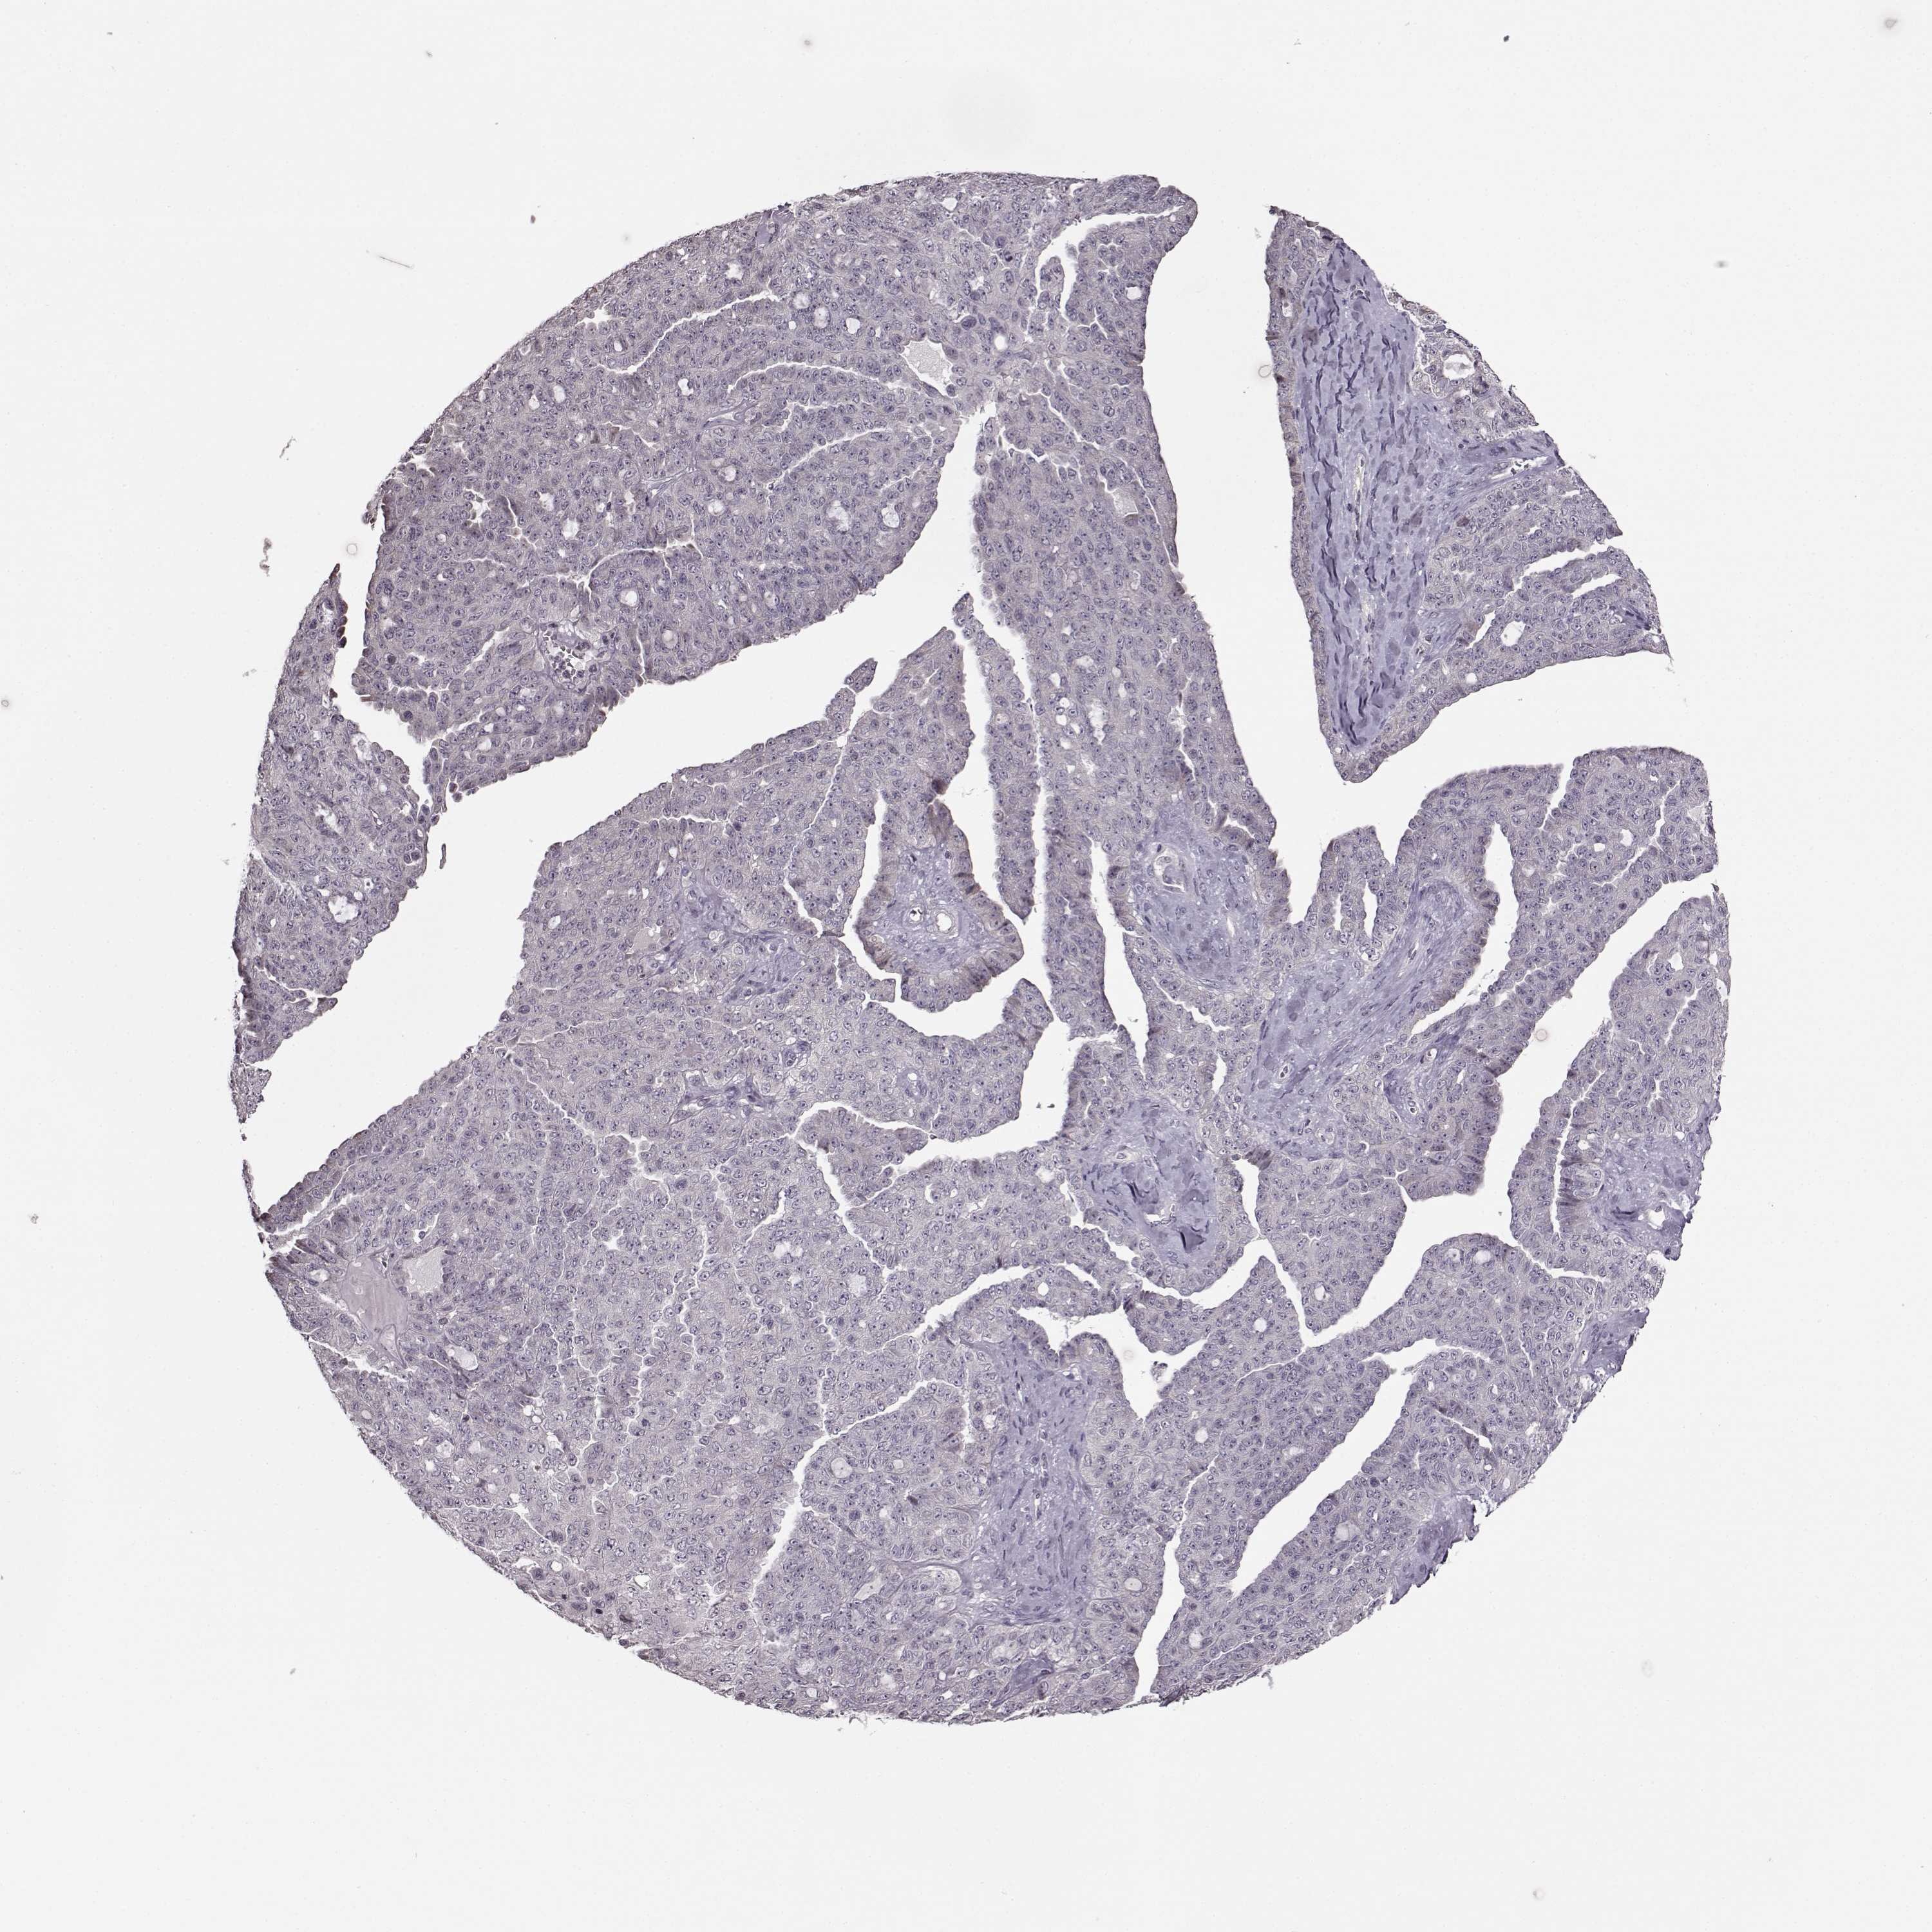

OVARIAN CANCER - Protein expressioni

A mouse-over function shows sample information and annotation data. Click on an image to view it in a full screen mode. Samples can be filtered based on level of antibody staining by selecting one or several of the following categories: high, medium, low and not detected. The assay and annotation is described here.

Note that samples used for immunohistochemistry by the Human Protein Atlas do not correspond to samples in the TCGA dataset.

Antibody stainingi

Antibody staining in the annotated cell types in the current human tissue is reported as not detected, low, medium, or high, based on conventional immunohistochemistry profiling in selected tissues. This score is based on the combination of the staining intensity and fraction of stained cells.

Each image is clickable and will lead to virtual microscopy that enables deeper exploration of all samples and also displays staining intensity scores, fraction scores and subcellular localization as well as patient and tissue information for each sample.

Cystadenocarcinoma, serous, NOS

Cystadenocarcinoma, mucinous, NOS

Carcinoma, endometroid